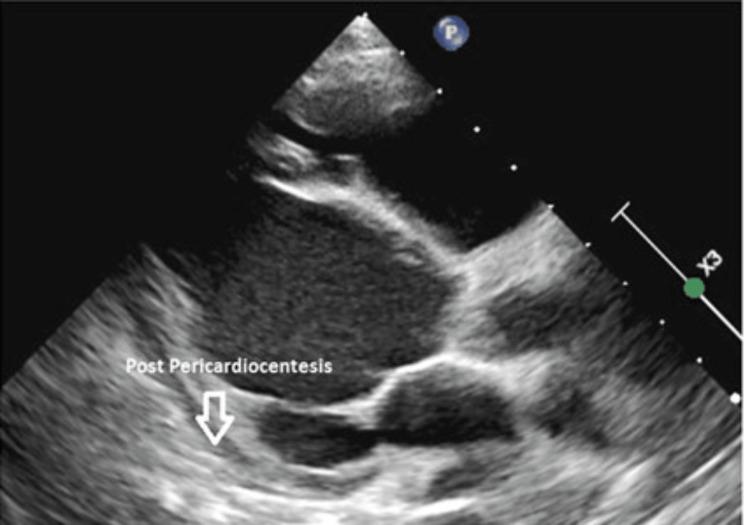

Pericardial effusion is an abnormal accumulation of fluid in the pericardial cavity. It can be associated with various cardiac and non-cardiac disorders. Dense deposit disease (DDD) is a rare kidney disease caused by uncontrolled activation of the alternative complement pathway. We are reporting a seven-year-old male child who was diagnosed to have DDD approved by renal biopsy and presented with shortness of breath, cough, and fever. Chest X-ray displayed cardiomegaly. Thereafter, echocardiography showed massive pericardial effusion and left ventricle compression with a risk for cardiac tamponade. He subsequently underwent pericardiocentesis with the removal of 450 ml of pericardial fluid. The patient's edema was not correlated with the described amount of drained pericardial fluid. To the best of our knowledge, this is the first reported case of significant pericardial effusion carrying the risk of cardiac tamponade associated with DDD. With this report, we would like to highlight the importance of cardiac assessment in patients with DDD, in particular those with nephrotic range proteinuria who present with cardiac symptoms and cardiomegaly.

心包积液是指心包腔内异常积聚液体。它可能与各种心脏和非心脏疾病相关。致密沉积物病(DDD)是一种由替代补体途径不受控制地激活引起的罕见肾脏疾病。我们报告一名七岁男童,经肾活检确诊为DDD,出现呼吸急促、咳嗽和发热症状。胸部X线显示心脏扩大。此后,超声心动图显示大量心包积液和左心室受压,有心脏压塞风险。他随后接受了心包穿刺术,抽出450毫升心包积液。患者的水肿与所描述的抽出心包积液量无关。据我们所知,这是首例报道的与DDD相关的有心脏压塞风险的大量心包积液病例。通过本报告,我们想强调对DDD患者进行心脏评估的重要性,特别是那些出现心脏症状和心脏扩大的肾病范围蛋白尿患者。